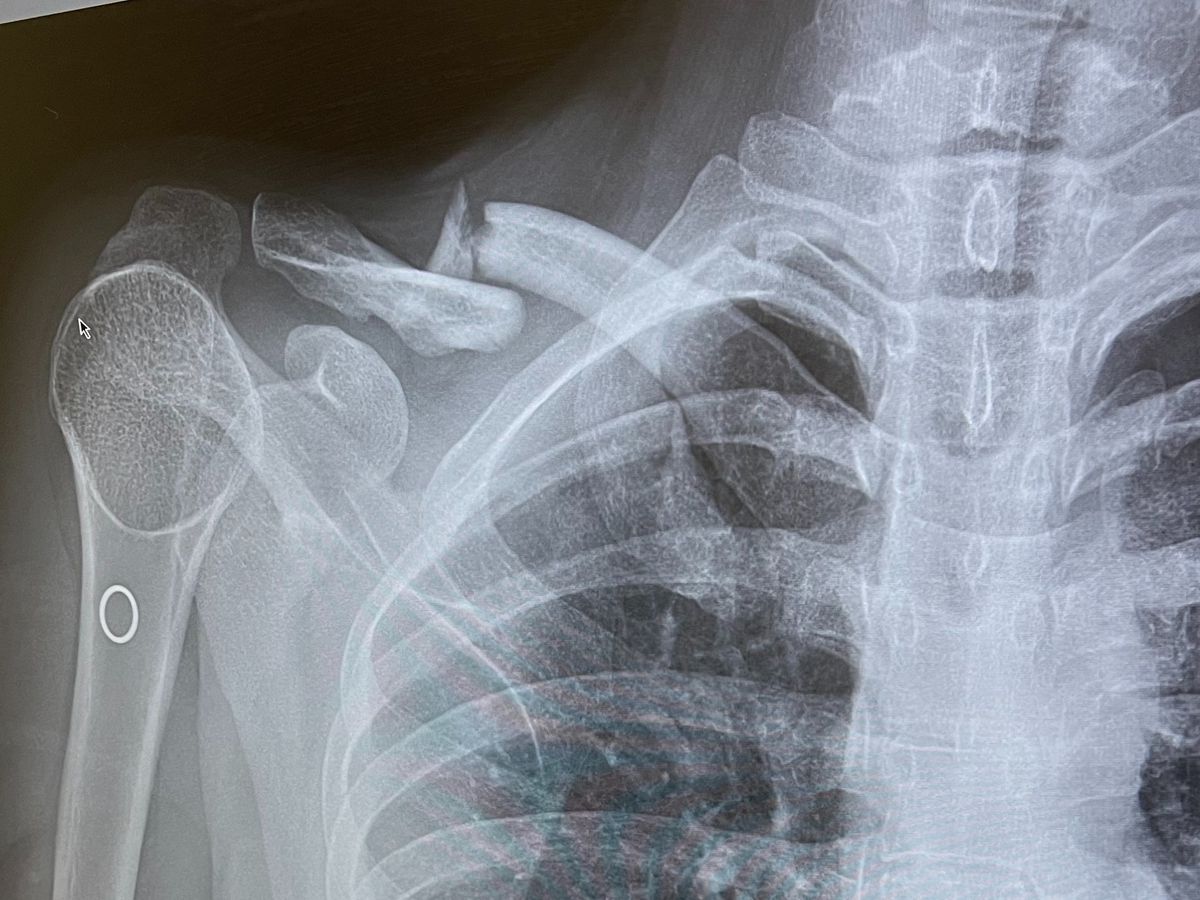

My friend Sammi broke her clavicle in three places and needs major surgery to fix it. Unfortunately, her insurance has very limited coverage and she is being required to pay $20,000 up front. Like most of us, Sammi does not have this kind of money saved up. She is unable to work because of her injury, so has no source of income. She has been knocked back from receiving a personal loan for medical expenses.